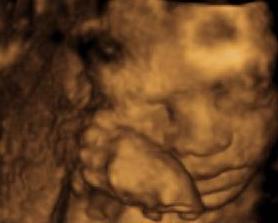

Ahoj holky, ta Vaše zlatíčka jsou náádherná!!!

Já měla poslední ultrazvuk u doktorky ve 12 týdnu, říká, že přesto, že nejsou prokázané vedlejší účinky, přecejen je to záření

pak jsem broučka ještě viděla, prakticky hotového na velkém ultrazvuku 8.ledna a to je vlastně všechno (váček, 12tt a 21tt) chjo, moc Vám závidím, že je máte alespoň každý měsíc na očích ... na druhou stranu, teď, když už se vrtí, mi to tolik nevadí, jako když jsem nevěděla nic a jen se strachovala ...

Hermí taky máš krásný UZ, Kajuško parádní fotky